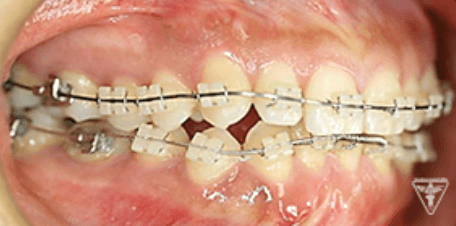

治療過程②